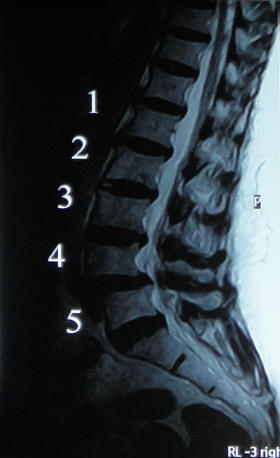

La Discólisis percutánea con ozono: es la infiltración del gas ozono directamente en el disco intervertebral herniado, mediante la punción con aguja guiada por intensificador de imágenes. Procedimiento, éste, que se realiza en quirófano, con el paciente sedado y monitoreado por un médico anestesiólogo. Duración del mismo: 30-40 minutos. Posteriormente permanecerá internado por un lapso de 12 a 24 horas, de acuerdo a la evolución. Con restitución del paciente a sus tareas habituales a las 48 horas de efectuado el procedimiento .